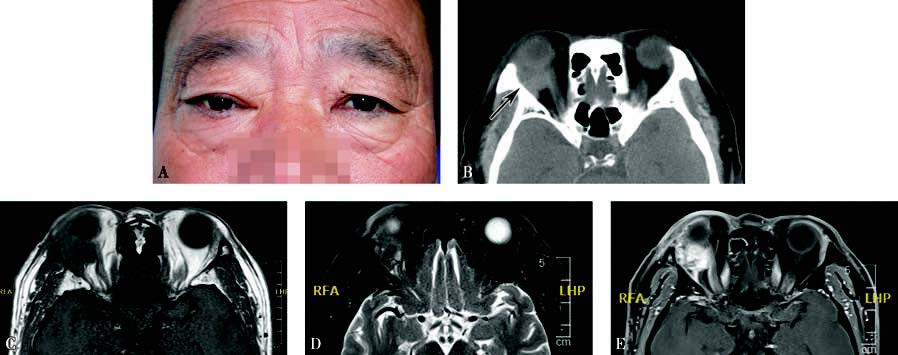

Figure 1 Appearance and imaging of pleomorphic adenocarcinoma of the lacrimal gland

A. External appearance of a patient with pleomorphic adenocarcinoma of the right lacrimal gland, showing right eye proptosis and ptosis of the upper eyelid.

B. Axial CT imaging reveals a hyperdnese extraconal orbital mass with no evidence of bone erosion (black arrow).

C. The tumor appears isointense on T1-weighted MRI.

D. MRI T2-weighted imaging with fat suppression reveals inhomogeneous signals within the tumor.

E. Contrast-enhanced T1-weighted imaging shows inhomogeneous enhancement of the tumor.